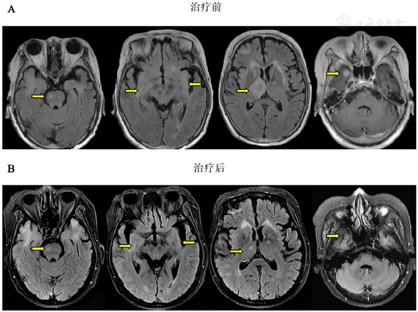

经过2个月的强的松治疗,嗜睡症状明显缓解,认知功能改善。复查头颅MRI示丘脑病变较前明显好转,复查胸部CT示双肺门、纵隔内多发肿大淋巴结及双肺结节均较前缩小。

脑磁共振成像(MRI)显示双侧大脑半球、右丘脑、右颞下叶多发病变(图1A)。胸部CT图像显示纵隔和双肺门淋巴结肿大并伴有多个肺结节(图2A)。18f -氟脱氧葡萄糖(FDG)正电子发射断层扫描(PET/CT)显示右上颈部深淋巴结、门部、纵隔、多发肺结节、双侧髋关节肌间隙、左髋关节皮下软组织明显摄取FDG(图3)。超声(US)引导下左髋关节皮下软组织活检显示大量嗜酸性粒细胞及纤维血管增生,无法提供诊断线索。然后我们在局部麻醉下对纵膈淋巴结进行WANG™经支气管抽吸针。然而,标本中仅发现少量纤毛柱状上皮细胞,诊断仍不明确。最后在全身麻醉下行支气管超声引导下经支气管针抽吸(EBUS-TBNA)纵隔淋巴结,发现慢性肉芽肿性炎症,提示结节病诊断(图4)。

文献报道,约5%至26%的结节病患者会出现神经系统并发症,在尸检研究中,患病率高达27%[6],这种累及神经系统的结节病,被称为神经系统结节病(Neurosarcoidosis, NS)。临床上,神经系统结节病的诊断往往依靠结节病多系统改变伴随神经系统表现,但必须先排除特殊病原菌感染及恶性肿瘤。由于神经系统结节病的组织学证据不易获得,因而当临床上怀疑神经系统结节病时,应先寻找神经系统以外疾病受累的证据。本病例以神经系统症状嗜睡起病,发病期间存在不规则发热,头颅MRI表现为右侧额叶、两侧颞叶、桥脑右侧、双侧基底节及侧室旁异常信号影,右侧丘脑病变伴周围水肿,胸部CT纵隔窗表现为双肺门、对称性淋巴结肿大,纵隔淋巴结肿大,胸部CT肺窗示表现为双肺散在多发结节,超声内镜引导下的经支气管针吸淋巴结活检提示慢性肉芽肿性病变,排除特异性感染后考虑结节病。该患者糖皮质激素治疗后未再出现发热,嗜睡及认知功能均较前明显改善,复查胸部CT示双肺门、纵隔内多发肿大淋巴结及双肺结节均较前缩小,复查头颅MRI示丘脑病变较前明显好转。故本病诊断肺结节病、神经系统结节病明确[7]。

本例患者存在嗜睡、认知功能障碍神经系统表现,MRI存在颅内多发病变,综合病情考虑结节病累及中枢神经系统可能。但是多种疾病都可以累及丘脑或下丘脑引起嗜睡及认知功能改变,故诊断需要结合临床表现、影像改变、组织病理学结果及治疗效果。本病例需与下列相关疾病进行鉴别:(1)细菌性和真菌性脑脓肿:在MRI上常表现为环形强化病灶,因此与胶质母细胞瘤或脑转移瘤相似,但弥散加权序列上存在明显的弥散受限以及有临床危险因素或感染征象[8];(2)胶质瘤:多发于儿童及青少年,发病无明显性别倾向,从发病到确诊,平均4~5个月,儿童及青少年往往以低级别胶质瘤为主,症状演变相对较快,预后相对较好,成人多为高级别胶质瘤;(3)丘脑静脉性梗死( thalamic venous infarction,TVI)是一种少见血栓栓塞性疾病,临床上比较少见,约占全部脑梗死0. 3% [9,10] ,以累及双侧病变多见,单侧病变非常罕见,多数见于左侧[2] ,最常见的原因是深静脉或静脉窦血栓形成导致丘脑静脉引流障碍[11];(4)脑转移瘤:脑转移瘤通常呈圆形且边界清楚,使用造影剂后可见强化,20%~ 30%的患者为单个脑转移瘤,其余患者为多发性脑转移瘤,肿瘤本身可能是实性、囊性或中央坏死性,在T1和T2加权像上可以呈低信号、等信号或高信号。几乎普遍呈造影增强;如果原本就存在已知有脑转移倾向的原发癌,则多发脑转移瘤患者无需进行活检,然而如果患者的原发肿瘤通常不会转移到脑部(例如,前列腺癌)、没有已知的原发病灶或神经影像学上不是典型的转移表现,可能需要活检或切除来确定脑部病灶的病因。(5)原发性CNS淋巴瘤(primary central nervous system lymphoma, PCNSL):是一种罕见的非霍奇金淋巴瘤,免疫功能正常和免疫功能低下的成人均可发生。免疫功能正常的患者中,PCNSL可以是孤立性或多灶性的。病变在T2加权像上呈等信号或低信号,使用造影剂后往往均匀增强,典型部位包括脑室周围白质、基底节和胼胝体。本病例无特异性感染、高热病史,暂不考虑细菌或真菌性脑脓肿,年龄不符合胶质瘤流行病学史,检查、检验结果及临床表现无明显栓塞征象,故不考虑丘脑静脉性梗死,其肿瘤指标未升高,肺部活检未见恶性细胞,颅内病变非肿瘤表现,故不考虑脑转移瘤,其颅内病变不符合原发性中枢神经系统淋巴瘤发病部位,综上所述,初步排除上述疾病。患者在使用糖皮质激素治疗后,嗜睡、认知功能明显改善,复查胸部CT及头颅MRI示病灶较前明显减小,淋巴结较前明显缩小,故神经系统结节病诊断明确,结合其头颅MRI表现及受累部位,考虑为累及丘脑的神经系统结节病。此患者颅内多发病变,丘脑较前吸收,但其他部位吸收不明显,考虑此现象为影像改变滞后,需再后续进一步随访,必要时可考虑行颅内病灶穿刺以协助诊断。

约2/3神经系统结节病患者呈单相病程,另1/3呈复发-缓解病程或伴间歇性加重的进行病程[14]。与普通结节病患者相似,神经结节病患者预后较好,10年生存率为89%[15]。多数患者通过上述的治疗方法都可以控制病情、改善预后。但是长期接受糖皮质激素或免疫抑制药物等治疗可能诱发多种严重不良反应,如免疫功能严重受损或增加患癌的风险,故治疗过程中应定期随访、评估疗效、观察是否出现不良反应及并发症。本例患者诊断明确后依据共识使用激素治疗几天后其嗜睡、认知功能明显改善,2个月后嗜睡完全缓解,甲状腺功能趋向正常,胸部CT及头颅MRI提示病变较前好转,淋巴结较前缩小,故未进一步使用免疫抑制剂等治疗措施,患者转归及预后仍需进一步随访。